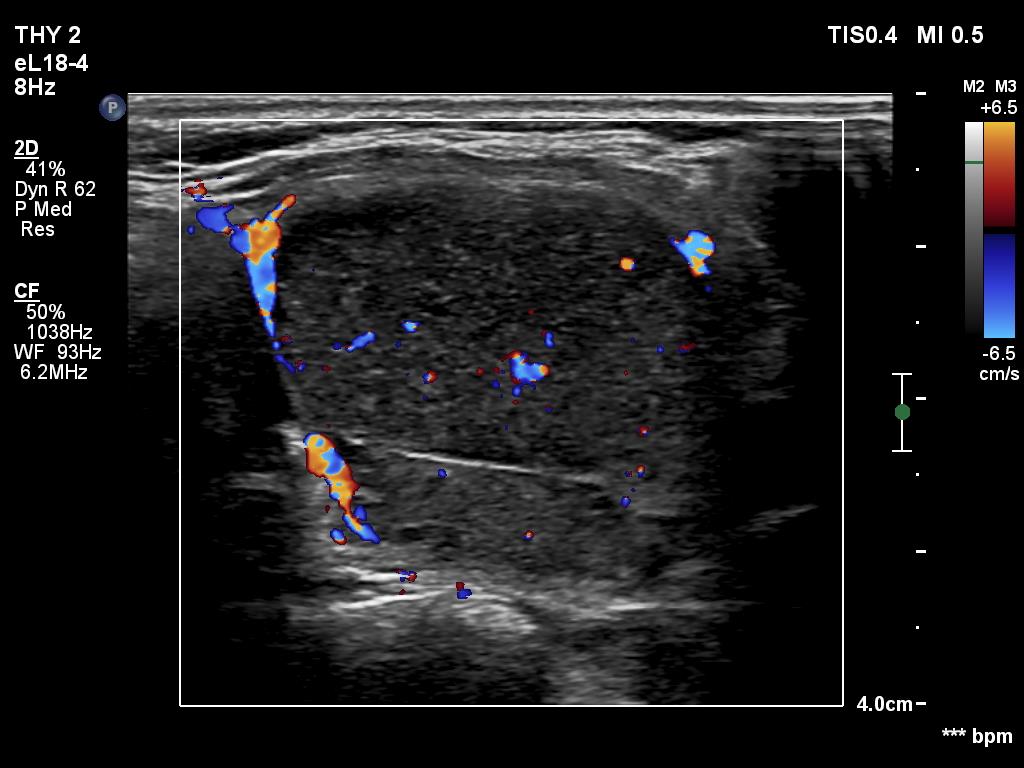

Halo sign and vascular pattern of nodules - case 1744 (ultrasonographic picture 7)

Left lobe, transverse scan, color Doppler mode - in another phase. The spots are seen in different locations.